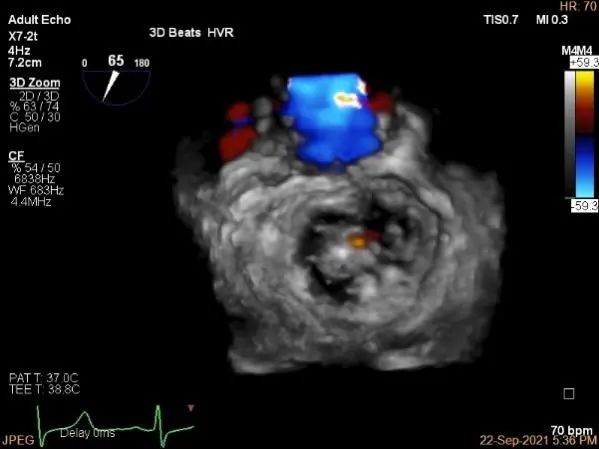

三维评估两个夹子位置

3D-color再次确定未见残余分流

评估瓣口条件,平均跨瓣压差:4mmHg

肺静脉血流频谱恢复正常